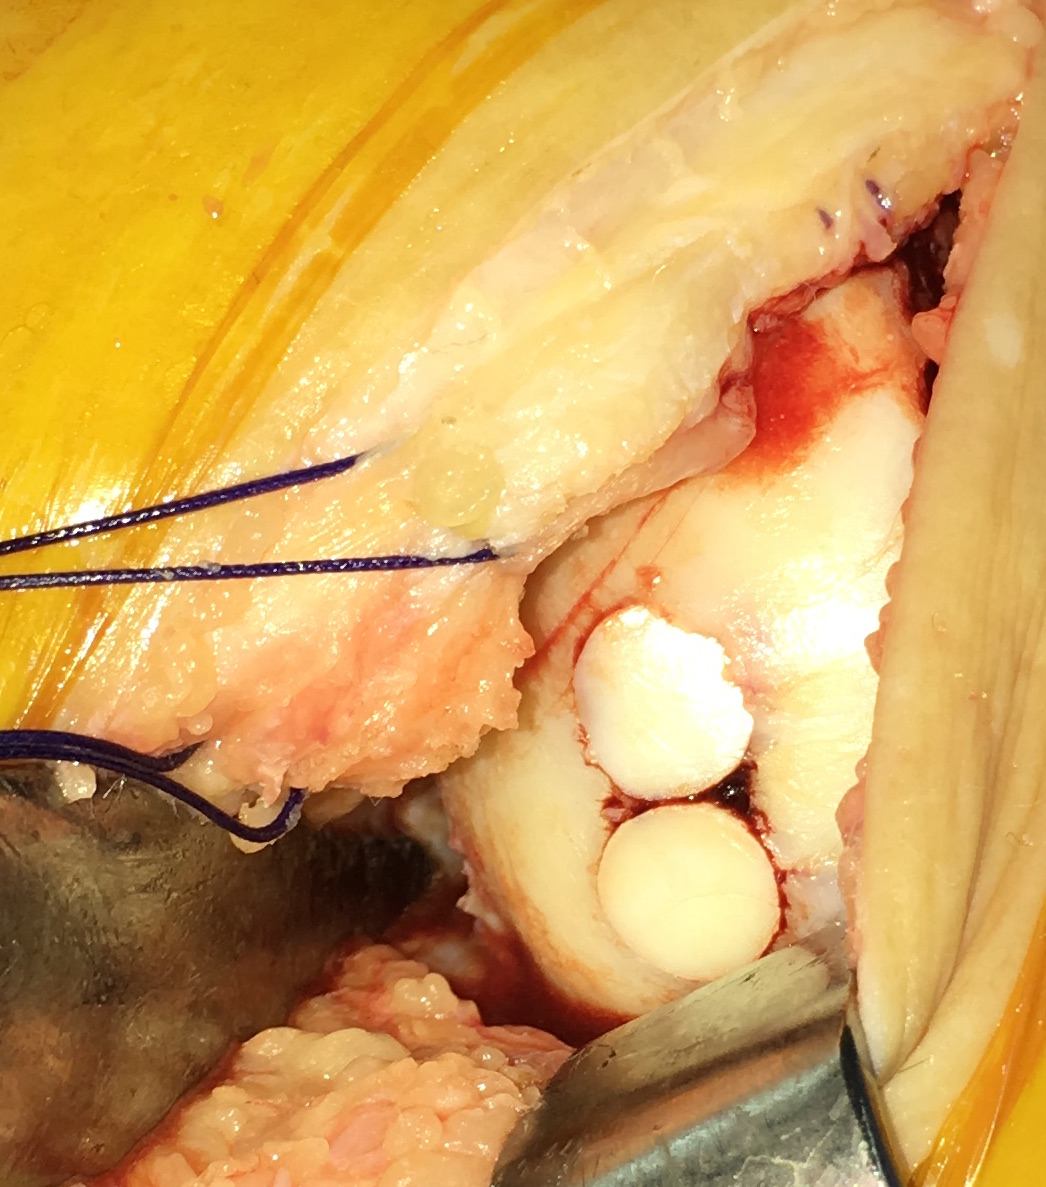

Trasplante osteocondral autólogo para tratar lesiones osteocondrales de la rodilla: evaluación de 62 pacientes con un seguimiento promedio de ocho años. [Osteochondral autograft transplantation for the treatment of osteochondral injuries of the knee: evaluation of 62 patients with an average follow-up of 8 years.]